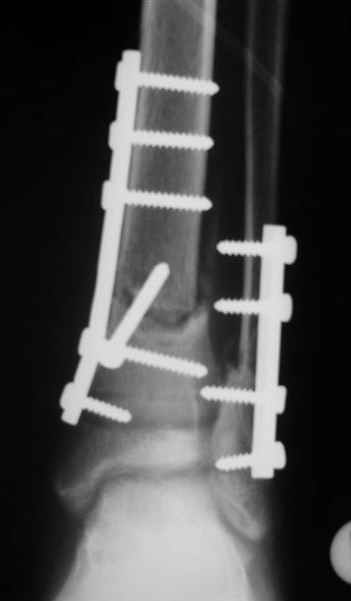

2

3a

3b

3c

PS.

В аттачте № 3 - один из примеров полукольцевого аппарат...

Это уже я баловался.

Итог? Работы больше (по времени и

интраоп "подгонке"), срастается также, а особого преимущества по сравнению с

"чиста" кольцевым (вес, удобство ношения и пр.) - я, по крайней мере,

не нашел.

Теперь не балуюсь.